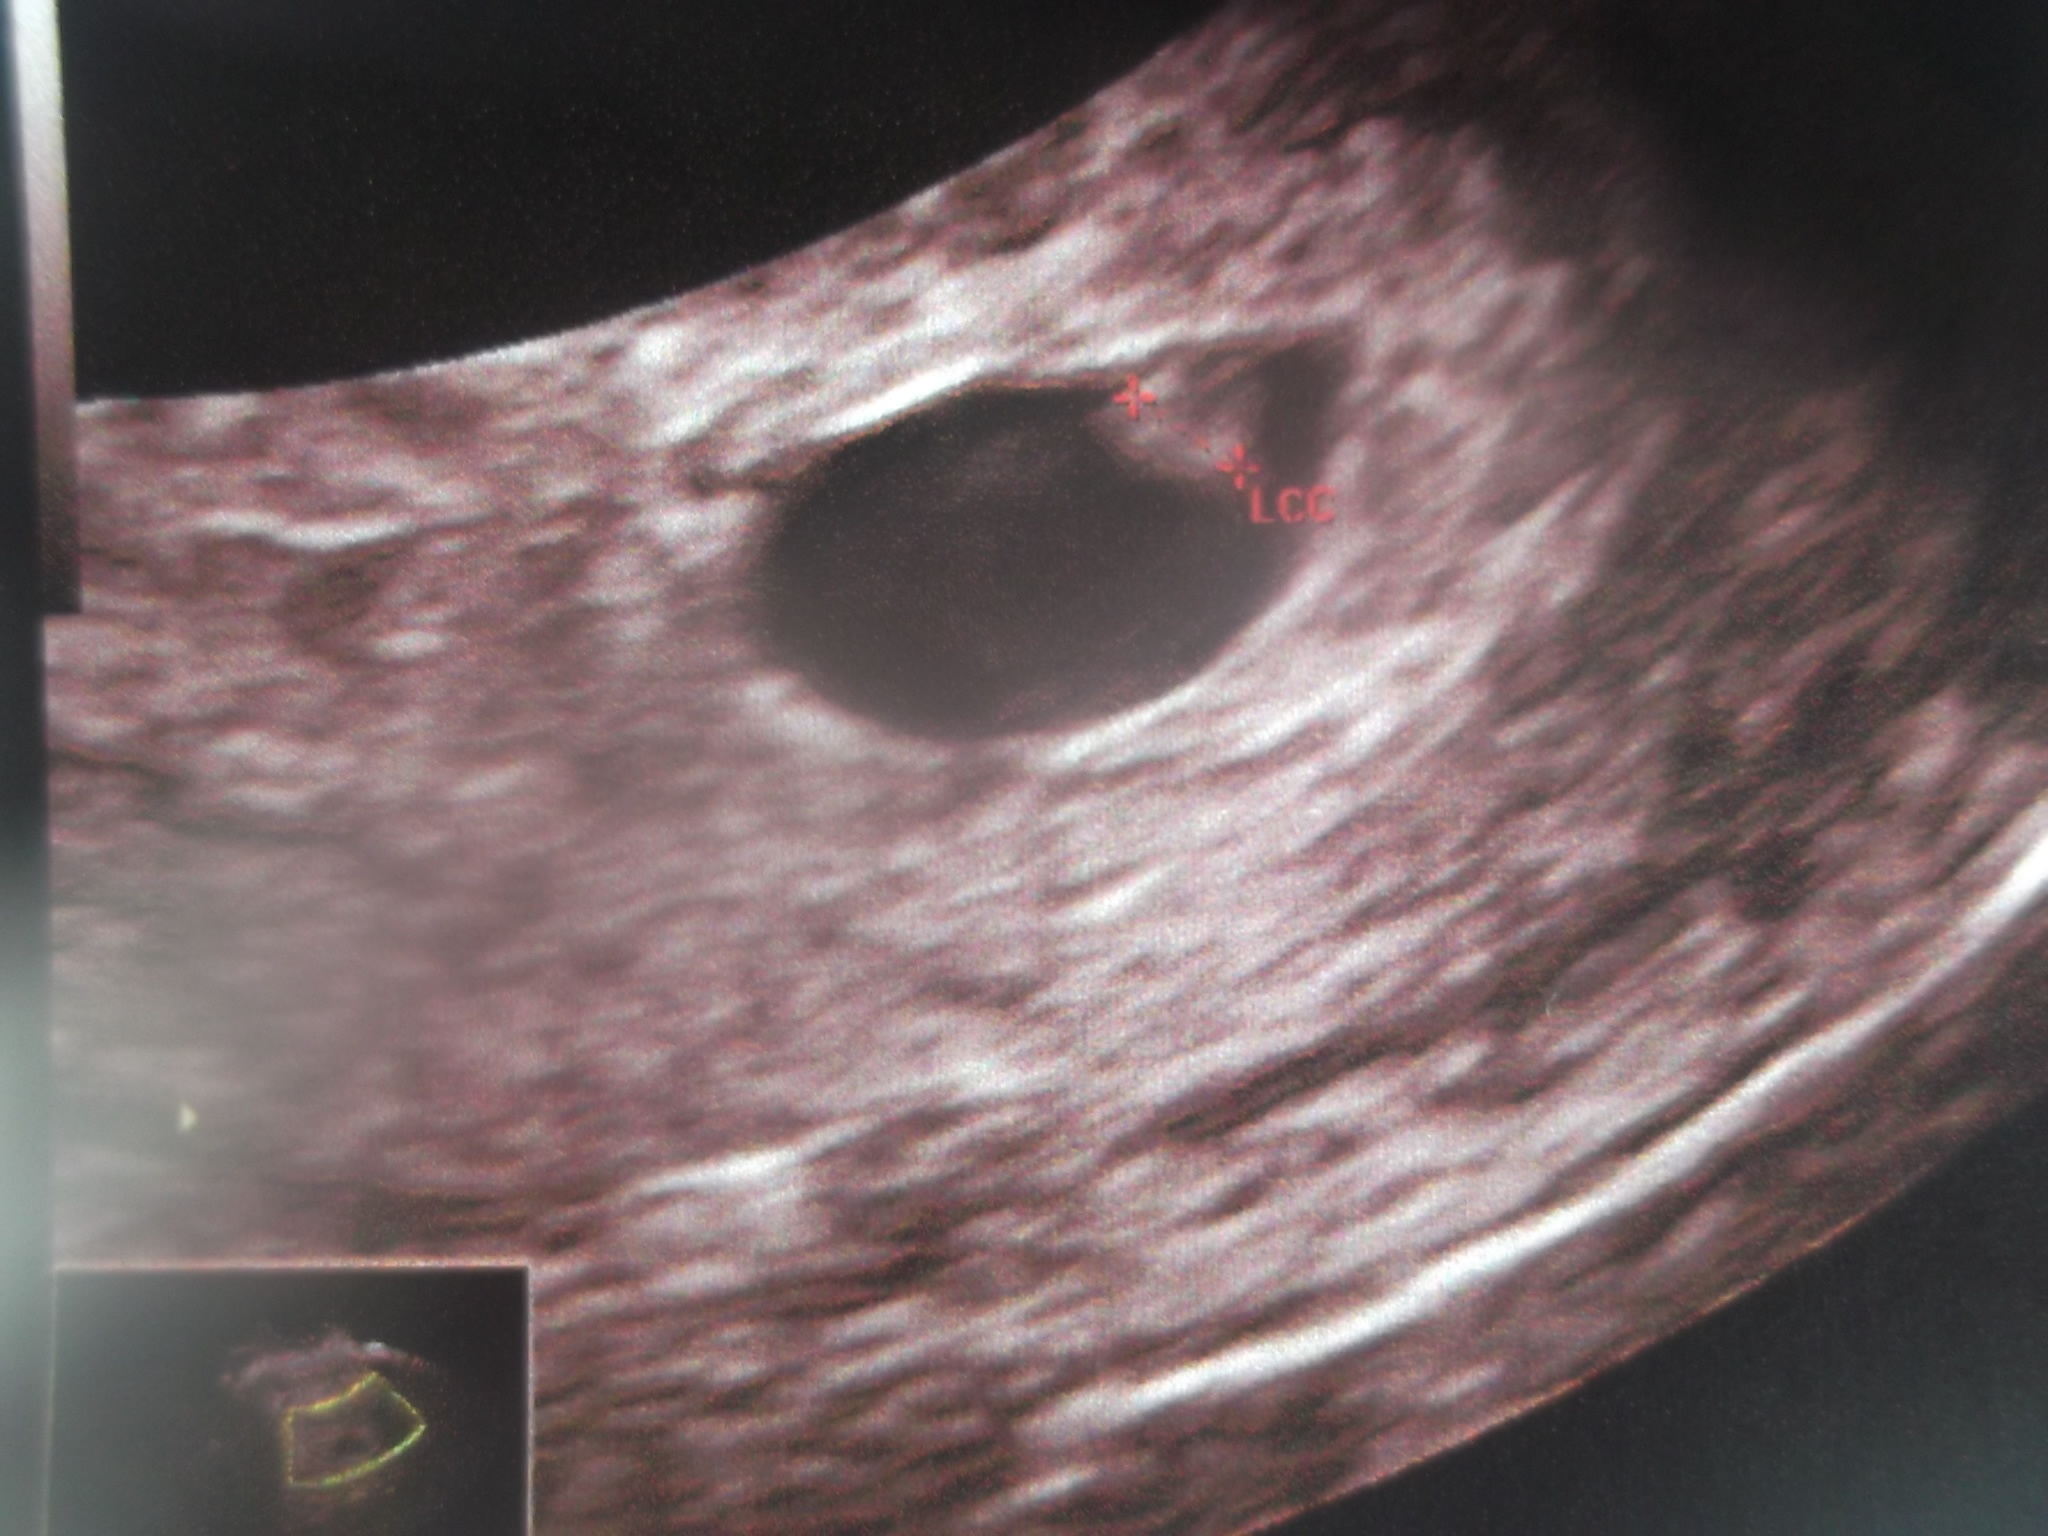

voila se que je peut te montrer et apparemnt je sui a 6sa

c'est le sac de grossesse qui mesure 12.9 mm et ce qui est dedant 2.5 mm